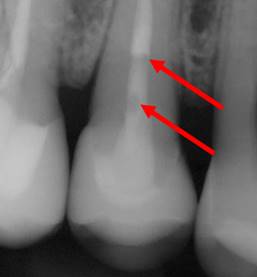

Bubbles visible on radiographs

In follow-up radiographs, two bubbles are visible for this endodontically treated tooth. It is embarrassing and hard to explain to patients. These bubbles drive endodontists crazy.